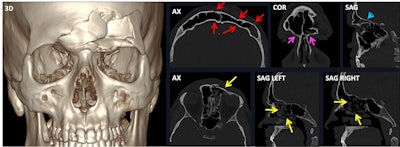

Bilateral frontal fracture involving both the anterior and posterior wall of both frontal sinuses (3D and red arrows). The fracture spreads inferiorly to both superior orbital rims (magenta arrows), posteriorly towards the anterior cranial fossa, with a resulting pneumocephalus bubble (blue arrow), and medially (yellow arrow in the axial view). Nevertheless, both frontonasal ducts remain intact (yellow arrows in sagittal views). AX = axial view, COR = coronal view, SAG = sagittal view, 3D = volume-rendered reconstruction. All figures courtesy of Dr. Mónica Régil Guerrero et al and presented at ECR 2025.

“The most commonly fractured structure in the frontal bone is the anterior wall of the frontal sinus, followed by both the anterior and posterior walls,” they stated. “Whenever the posterior wall alone is fractured, the skull base and cranial vault should be examined, as they could harbor the source fracture.”

Frontal fractures can occur in three ways:

- Inferiorly: The superior orbital rim will be involved.

- Medially: The frontonasal duct should be checked because this is the drainage tract of the frontal sinus into the nasal cavity, through the middle nasal meatus; when this is fractured, a mucocele can arise.

- Posteriorly: The anterior cranial fossa is immediately behind the frontal bone; therefore, cerebrospinal fluid leak, encephalocele, pneumocephalus, and traumatic or infectious intracranial complications may occur.